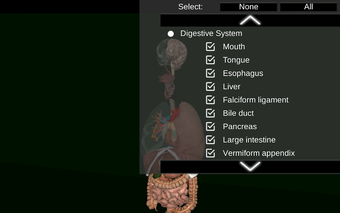

Diese Anwendung zeigt ein dreidimensionales Modell der menschlichen Körperorgane und eine Beschreibung aller von ihnen.

Sie können jedes Organ wie Herz, Gehirn, Lunge, Fortpflanzungssystem, Leber, Darm, Eierstock, Hoden, Magen, Niere usw. anfassen.

Die Anwendung soll das Studium der Anatomie in Medizin, Biologie oder anderen Fächern ergänzen.

Sie ist für alle Menschen nützlich, auch für Studenten, da jedes Anatomieorgan in einer anderen Farbe dargestellt ist.